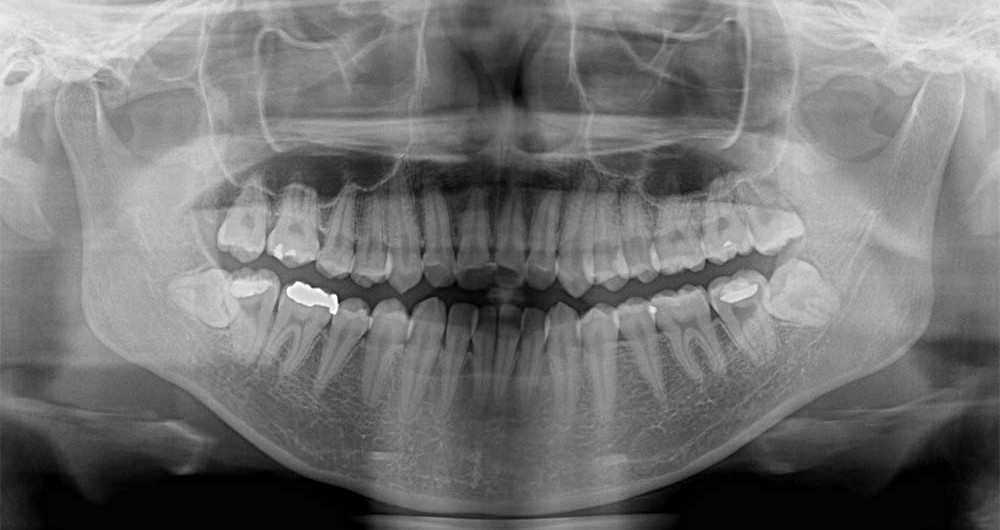

20代男性

ケース3:左下に食べ物がつまる

県内の歯科医院より紹介頂き受診されました。初診の当日に処置を行っています。

神経と歯の根が近かったためCTにて位置関係を3次元的に確認したうえで、5mm程度の切開を行い歯の頭の部分を削って抜きました。2糸縫って終わっています。

術後は紹介先で経過を診て頂いていますが、少しの腫れはあったようですが痺れ等はなかったようです。

- 所要時間

- 15分程度

- 費用

- ¥9,000(健康保険内)